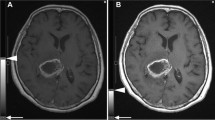

In the present study, both an iPad Air™ device and a medical LCD monitor were used to read MRI scans and accurately diagnose acute ischemic cerebrovascular disorders. No significant difference was found between the diagnostic results obtained from the scans viewed on an iPad Air™ device as compared with those viewed on an LCD medical monitor. We believe that the excellent contrast in diffusion-weighted images is one of the reasons for the comparable performance of the two devices. Further study regarding the detectability of acute ischemic cerebrovascular disorders on CT images, which is known to be more difficult, is required to determine the degree to which the nonuniformity of luminance due to the directionality of LCD screen backlighting affects the results.

The present study has some limitations. First, MRI scans were used to diagnose acute cerebral infarction in the image interpretation experiments. Compared with CT scans, MRI scans have better contrast, which could have reduced potential differences in image interpretation. In addition, four different types of MRI scanners were used, and although the characteristics of the control group for each scanner were similar, we cannot eliminate the possibility of selection bias. Secondly, the analyzer used in the present study is the Luminance and Chromaticity Uniformity Analyzer UA-10, and although precision was maintained during assessments and comparisons between similar monitors, it is not a spectral luminance meter. Although luminance was assessed using an iPad Air™ device and an LCD medical monitor, assessment was not performed with the calibration of spectral luminance meters, thereby suggesting that limited comparison of luminance among various monitors should be considered. Furthermore, in the present study, assessments were made using an earlier model iPad Air™ tablet. New tablet models are commercially available each year; hence, our results may not be entirely applicable to all models. Lastly, TIA cases in clinical settings may not always exhibit high signal intensity on diffusion-weighted images. Among those who showed no abnormal MRI findings, we designated subjects who did not experience acute cerebral infarction during the entire clinical presentation as “normal” cases. In contrast, among the subjects in the acute cerebral infarction group, two were discharged because no abnormal findings were noted on MRI scans obtained in the emergency department; and thus, were determined not to have experienced acute cerebral infarction based on clinical signs. After a few days, these two subjects underwent repeated MRI; since these additional studies indicated that the lesions with weak signal intensity on diffusion-weighted images should have been detected, we included the first and second MRI studies in the acute cerebral infarction group. Images of a patient who showed no signs of acute cerebral infarction but experienced one several days later were included. In the present study, no differences were found between the LCD medical monitor and the iPad Air™ device in terms of lesion detection rates as abnormalities. As such, when the detection of abnormalities is impossible or when the diffusion-weighted images show no clear lesions, more attention should be paid to detailed clinical examination. Although we did not assess MR angiography (MRA) in the present study, no contrast- or clarity-related issues have been reported during the use of mobile devices to observe CT angiograms and MRA [23]. Our results suggest that the contrast of the iPad Air™ device does not differ from that of the LCD medical monitor and that the use of the iPad Air™ device to examine MRA studies is unlikely to pose any problems.